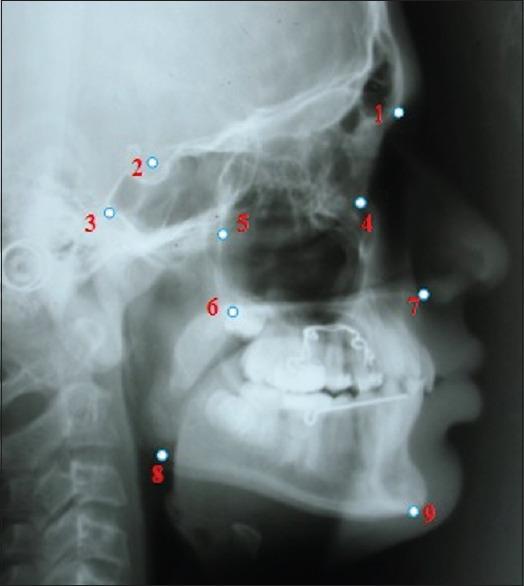

Pretreatment and postdistalization lateral cephalograms and study models of 20 subjects (6 males, 14 females) Class II malocclusion subjects were examined. PA and JJ group both consisted of 10 patients each with a mean pretreatment age of 12 years 1 month for females and 12 years 5 months for males. The PA and the JJ appliance were activated once in a month until Class II molar relationship was corrected to a super Class I molar relationship in both groups. Initial and final measurements and treatment changes were compared by means of Paired -test.

Maxillary first molar distalized an average of 3.85 mm in the PA and 2.75 mm in the JJ between T1 and T2; rate of molar distalization was 1.59 mm/month for PA, and the JJ appliance averaged 0.88 mm/month, distal molar tipping was greater in PA (6.2°) than in the JJ (3.9°). Average mesial movement of the premolars was 2.2 mm with PA and JJ both. JJ showed a greater rotation of first molars after distalization as compared to PA. The increase in vertical facial height was also greater for JJ as compared to PA.